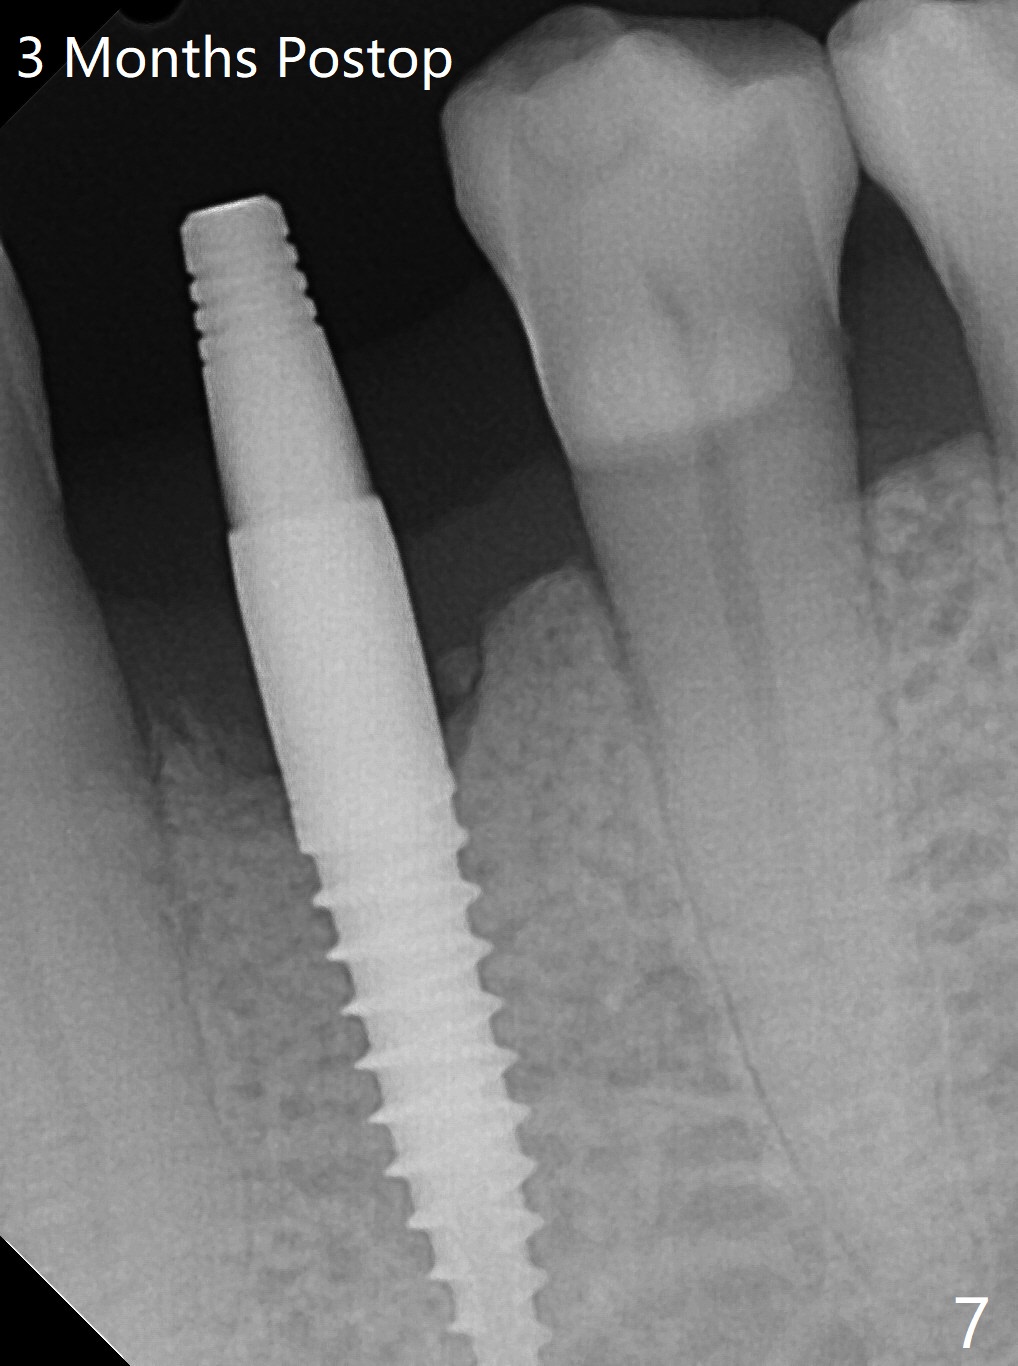

After incision at #21 (Fig.1) and flap elevation, the narrow ridge is reduced and initial osteotomy is made (Fig.2,3). Following moving the osteotomy distal, a 3x12(4) mm 1-piece implant is placed with >35 Ncm (Fig.4-6). Vanilla Graft is placed in the most concave buccal defect (Fig.1,4 *) and over the ridge reduction area (Fig.6 *). No bone loss is observed 3 months postop (Fig.7).